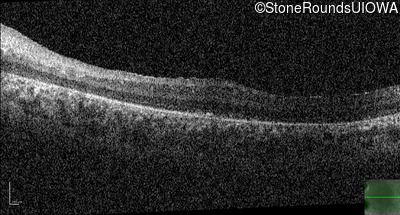

Age at visit: 15 years

This 15 year old male has had very poor vision and nystagmus since the first year of life.

Age at visit: 17 years